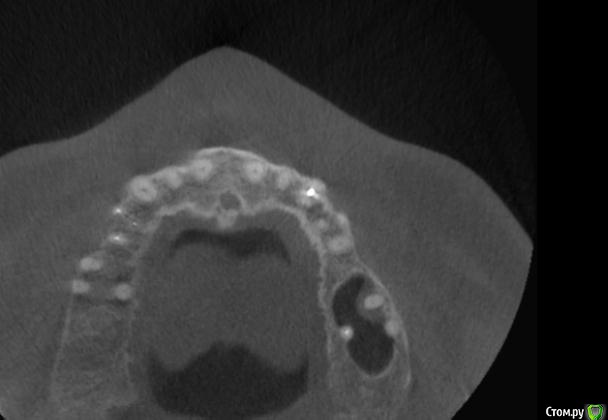

platerx Опубликовано 21 декабря, 2015 Поделиться Опубликовано 21 декабря, 2015 (изменено) Всем доброго времени суток.У меня есть пара вопросов: 1. Что можно сделать с зубом 2.7 История зуба такова:Зуб был сильно разрушен, но мне предложили попробовать пролечить его. Прочистили каналы, я некоторое время ходил с лекарством в зубе. Затем запломбировали каналы и поставили вкладку и коронку (консоль). Это было 2,5 года назад.С тех пор зуб меня иногда немного беспокоил, вызывая некоторый дискомфорт, но я не сильно обращал внимание. В последнее время он стал беспокоить сильнее: время от времени вызывает тянущие и распирающие ощущения, которые усиливаются при нажатии. Слегка побаливает десна и небо с внутренней стороны. Периодически ощущения пропадают. Прикладываю срезы КТ этого зуба. Что можно сделать с этим зубом ? Можно ли извлечь вкладку и перелечить каналы ? 2. При депульпировании зуба 2.4 врач не промывал каналы гипохлоритом (только хлоргексидином), после чего запломбировал их. Это нормально или стоит переделать? На зубе сейчас временная пломба, по прошествии 6 дней зуб не беспокоит. При постукивании есть небольшие неприятные ощущения. Изменено 21 декабря, 2015 пользователем platerx Ссылка на комментарий

DmitrySH Опубликовано 21 декабря, 2015 Поделиться Опубликовано 21 декабря, 2015 Добрый вечер.27. Есть очаг воспаления на одном из корней. Нужно снять коронку, оценить объём тканей. Если все ок, то извлечение вкладки и ревизия каналов.24. Сложно дать однозначный ответ. После выяснения ситуации с 27 планировать имплантацию в области 26 или 26, 27 (если с 27 все плохо) Ссылка на комментарий